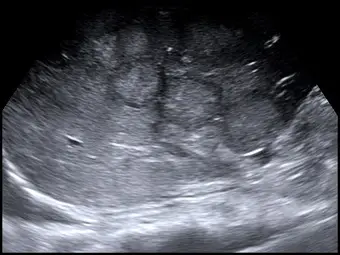

女性患者有癌症病史,肝臟超音波掃描時,發現多個病灶,且其邊緣呈現低回音性暈環( hypoechoic halos),根據下圖最有可能的診斷為何?

- 灰階超音波影像:本題提供的肝臟超音波影像中,可以清楚觀察到肝臟實質內散佈著「多發性(multiple)」的結節狀病灶。

- 回音特性:這些病灶的中心區域呈現相對等回音(isoechoic)或稍微高回音(hyperechoic),而最關鍵的特徵在於其周圍皆包覆著一圈明顯的**「低回音性暈環(hypoechoic halo)」**。

- 經典徵象:此種「中心高/等回音,外圍低回音暈環」的視覺呈現,在超音波影像學上被稱為經典的**「牛眼徵(Bull's eye sign)」或「靶心徵(Target sign)」**。外圍的低回音暈環在病理上通常代表著腫瘤邊緣活躍增生的癌細胞,以及被腫瘤推擠而受壓迫的正常肝臟實質組織。

- (A) 轉移性肝癌(liver metastasis):正確。當超音波發現肝臟有多發性病灶,且具備典型的「牛眼徵」或「低回音性暈環」時,高度提示為惡性腫瘤。再加上題幹明確指出該女性患者有「癌症病史」,臨床上首先必須考慮的就是癌症發生肝臟轉移。